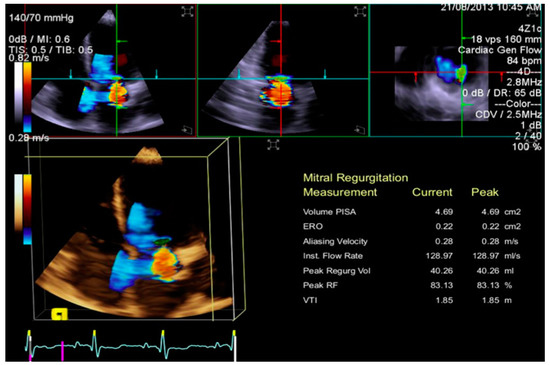

3.3. Quantification of Mitral Regurgitation